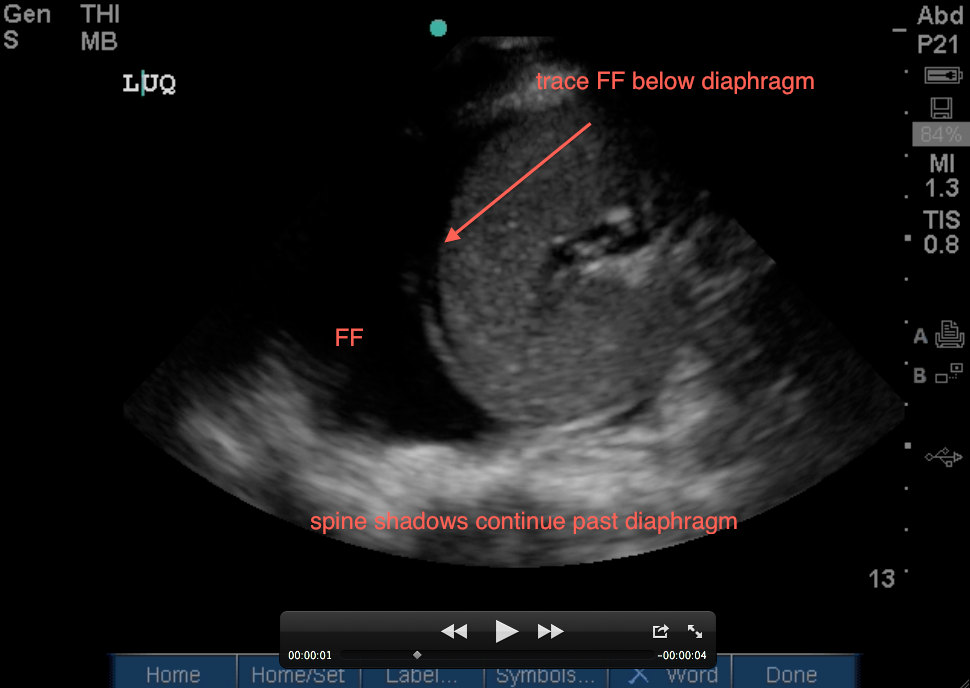

1. Evaluate above the diaphragm…. to evaluate for intrathoracic free fluid. This may involve having to increase your depth while you slowly fan your probe anterior to posterior (from 13cm to 16cm – you dont usually need to go 19cm unless it’s a huge spleen). The patient’s breathing will also help you as you will notice the bright white (echogenic) linear diaphragm which hugs the spleen will move (right and left) on your screen with every breath. Having the patient take a deep breath and holding it, will allow you better visualization if a rib shadow is in your way. A mirror image of the spleen may be seen above the diaphragm (a normal artifact that occurs when ultrasound passes through structures of varying densities and then through air (lung). However, in the LUQ, If no mirror image, it may not mean free fluid, especially if the stomach is in your view. If the area above the diaphragm is truly anechoic (black) without Stomach Sabotage – that’s fluid in the thoracic cavity! The spine sign will also help you evaluate for free intra-thoracic fluid, as the spine and it’s shadowing normally stops once it hits the diaphragm when visualizing on the screen from right to left (air is the enemy of ultrasound!). But if there is fluid in the thoracic cavity, you will see the spine continue to traverse past the diaphragm up into the thoracic area (fluid is the lover of ultrasound!).

2. Evaluate below the diaphragm… to evaluate for intraperitoneal fluid. This is where free intraperitoneal fluid will usually develop first in the left upper quadrant (LUQ) (different from the RUQ where the first area of free fluid is usually around the inferior pole of the kidney and right paracolic gutter). If you increased your depth for #1 above, you will need to adjust it back. You will be sabotaged by stomach when getting this view, so you may want to oblique your probe (indicator toward gurney as explained by Dr. Mike Stone) in plane with the ribs and angle your probe posteriorly (and thus away from the anterior stomach). Black fluid below the diaphragm between it and the spleen is abnormal as seen below: